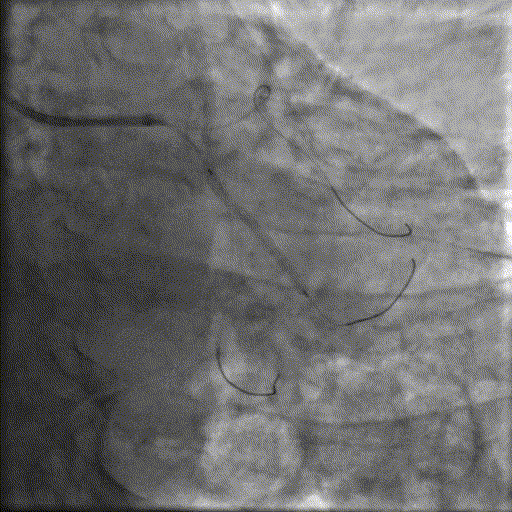

冲击波球囊治疗

2.5*12mm@4atm 冠脉血管内冲击波导管反复进行8个周期治疗,经IVUS检查提示最小管腔面积增加至4.88mm²;随后选取后扩张球囊对病变行扩张治疗。

支架植入并后扩

于LM-LAD依次植入两枚药物洗脱支架,经非顺应性球囊后扩张支架,复查造影&IVUS提示血管内钙化仍较重,支架贴壁不良,遂再次启动IVL治疗。

再次冲击波球囊治疗

3.0*12mm@4atm 冠脉血管内冲击波导管反复进行5个周期治疗,并选取后扩张球囊对病变行扩张治疗。最终复查造影提示残余狭窄小于10%,未见夹层及血肿,TIMI血流3级。